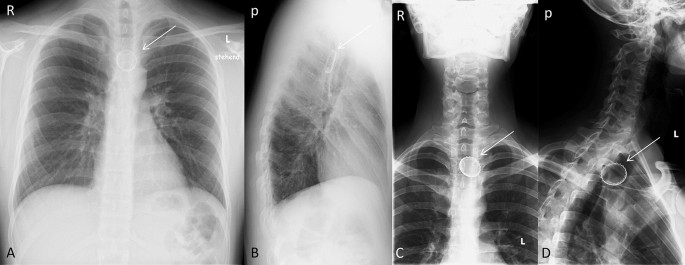

In all patients, there was radiographic proof by chest or neck X-ray of a bottlecap stuck in the esophagus. 10 (71.4%) were localized in the cranial third of the esophagus, 3 (21.4%) were localized in the middle third of the esophagus and 1 (7.1%) was localized in the caudal third of the esophagus (Figs. 1, 2, 3). Interestingly, in all imaging findings, the bottlecap has nearly the same alignment in space, flat parallel to the spine.

Upper esophageal narrowing. The upper esophageal narrowing lies at the level of near cervical vertebrae VI/VII, about 15 cm measured from the front row of teeth. A, B: Posterior–anterior X-ray (A) and left-sided lateral X-ray of the thorax (B). Bottlecap near thoracic vertebra I/II (arrow). C, D, E: Anterior–posterior (C) and left-sided lateral X-ray of the cervical spine (D). Posterior–anterior X-ray of the thorax (C). Bottlecap near cervical vertebra VII and thoracic vertebra I (arrow). R right; L Left; a anterior; p posterior

Middle esophageal narrowing. Point where the esophagus passes by the aorta and the left main bronchus. It lies at the level near of thoracic vertebrae IV. This is about 10 cm caudal to the upper narrowness. A, B: Posterior–anterior X-ray of the thorax (A) and left-sided lateral X-ray. Bottlecap near thoracic vertebra IV/V (arrow). C, D: Anterior–posterior (C) and left-sided lateral X-ray of the cervical spine (D). Bottlecap near thoracic vertebra II/III (arrow). R right; L Left; a anterior; p posterior